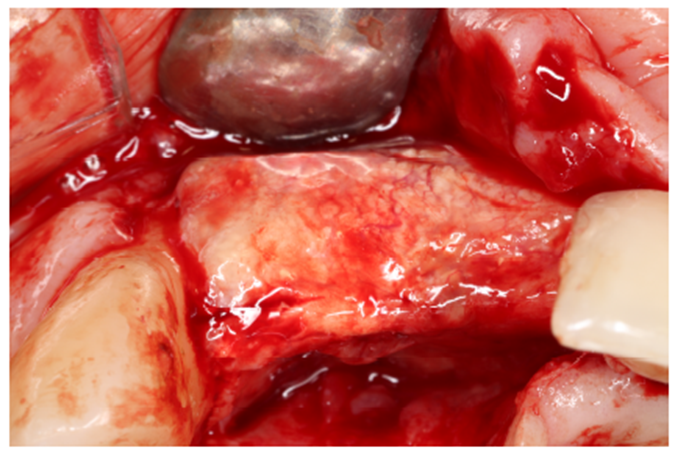

Nos casos de extensa reconstrução óssea, o retalho cirúrgico deve ser realizado à distância para visualização total da área cirúrgica, acomodação do seu futuro material de enxerto, ganho e fechamento total do tecido mole (Figura 4). Outro ponto importante para o sucesso da integração do material de enxerto é a descorticalização do processo alveolar, a fim de levarmos sangue medular com maior quantidade de células osteoprogenitoras. No caso, foi realizado com uma broca tipo lança.

Após a descorticalização, a membrana de PTFE-d (Cytoplast) foi aberta para modelagem e adaptação no rebordo, visando o acomodamento do material de enxertia. Ela foi parafusada na cortical palatina facilitando a inserção do material via vestibular. (Figuras 5 e 6).